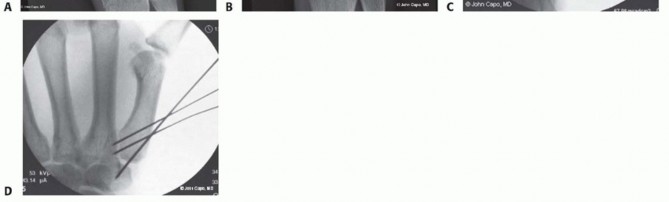

CRPP is the treatment of choice for classic Bennett fractures where the volar-ulnar fragment is too small to reliably accept a lag screw, yet the joint can be anatomically reduced closed. The reduction maneuver is highly specific, designed to counteract the deforming forces of the APL and Adductor Pollicis. Longitudinal traction is applied to the thumb, followed by palmar abduction and pronation. Direct pressure is then applied to the dorsal-radial aspect of the metacarpal base, effectively pushing the shaft back into the anatomic cradle of the intact volar-ulnar fragment.

Once anatomic reduction is confirmed via multi-planar fluoroscopy, percutaneous fixation is achieved. Typically, two 0.045-inch or 0.062-inch Kirschner wires are utilized. The first wire is driven from the dorsal-radial aspect of the metacarpal shaft directly into the trapezium, effectively neutralizing the proximal pull of the APL. A second wire is often placed transversely from the first metacarpal shaft into the second metacarpal to control rotation and maintain the web space. Pins are cut outside the skin and capped to facilitate easy removal in the clinic.